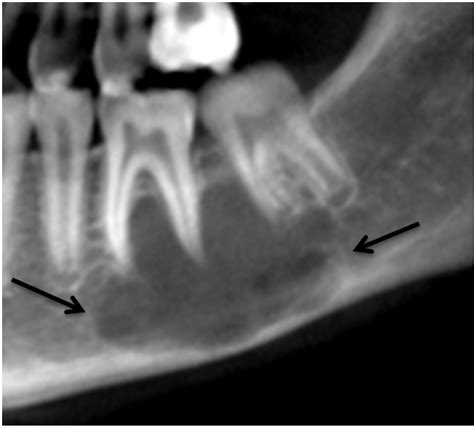

The radiographic appearance of a traumatic bone cyst can vary, but some common features include:

• Well-defined Radiolucent Lesion: The cyst appears as a well-defined, radiolucent area on dental radiographs.

• Scalloped Margins: The margins of the cyst may be scalloped, giving it a characteristic appearance.

• Cortical Bone Expansion: In some cases, the cyst may cause expansion of the cortical bone.

• No Internal Structures: Unlike other cysts, a traumatic bone cyst typically does not contain internal structures such as septa or calcifications.

Here is a table summarizing the radiographic features of a traumatic bone cyst:

Feature Description

Shape Well-defined, radiolucent

Margins Scalloped

Cortical Bone May be expanded

Internal Structures None